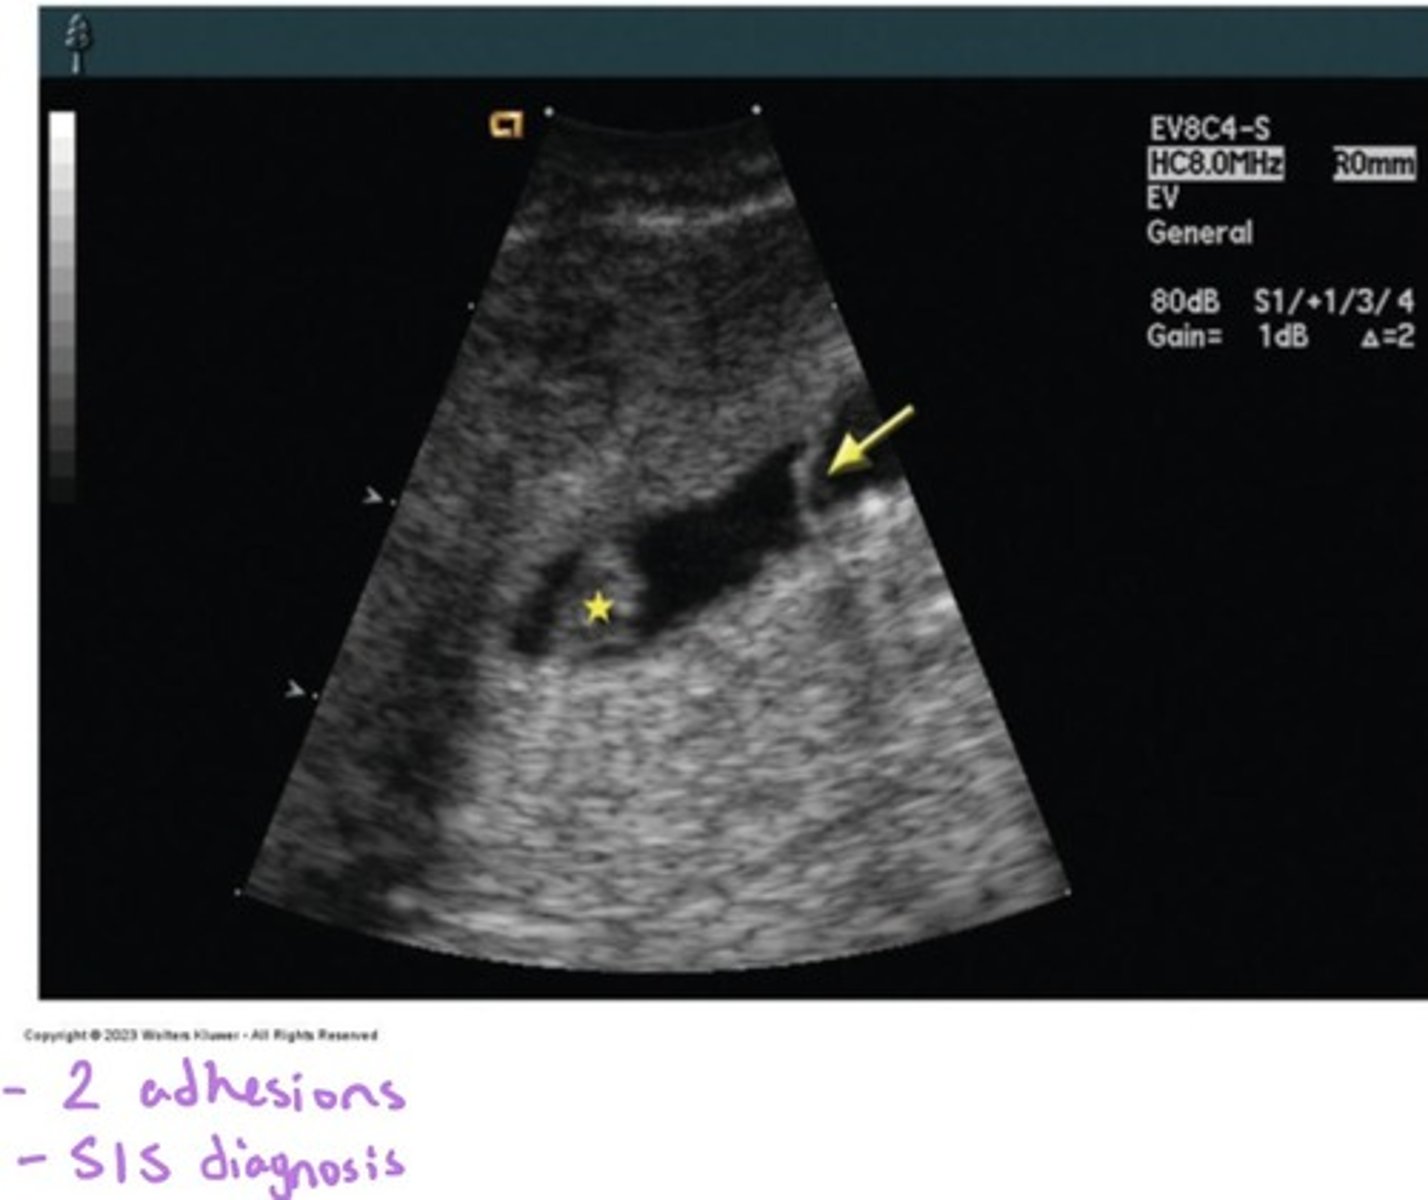

What are the diagnosis methods for Asherman's Syndrome? (HINT: 3)

HSG, SHG, hysteroscope

How do adhesions appear on SIS?

Adhesions appear as echogenic bands